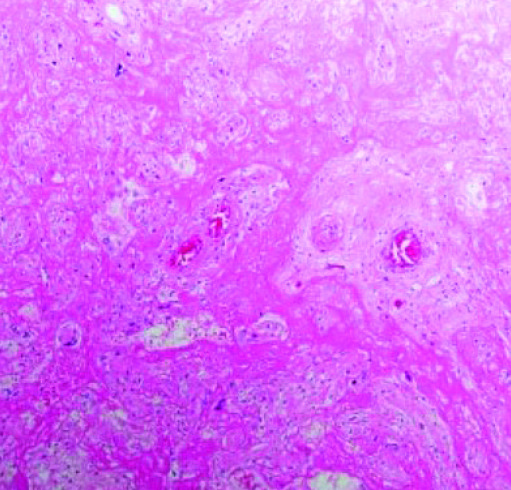

Массивное выпадение фибрина (см. рис. 3) — очень заметный и яркий признак. Иногда ворсины настолько замурованы выпавшим фибрином, что их трудно найти и рассмотреть, циркуляция материнской крови нарушена. Газообмен в плаценте значительно снижается или вовсе прекращается, что ведет к гипоксии и гибели плода.

Сканируя гистологические препараты на малом увеличении, мы видели крупные участки тромбоза с массивным выпадением фибрина в межворсинчатом пространстве. На большом увеличении в периферии участков тромбоза наблюдается воспалительная инфильтрация в ворсинах и межворсинчатом пространстве. Можно рассмотреть, как фибрин буквально заклеивает собой ворсины.

В основном это свежий фибрин, хотя наблюдаются и участки более зрелого фибрина. То есть на морфологическом уровне мы предполагаем, что поражение плаценты происходит достаточно быстро и ведет к гибели плода. Все это подтверждается и клиническими данными.